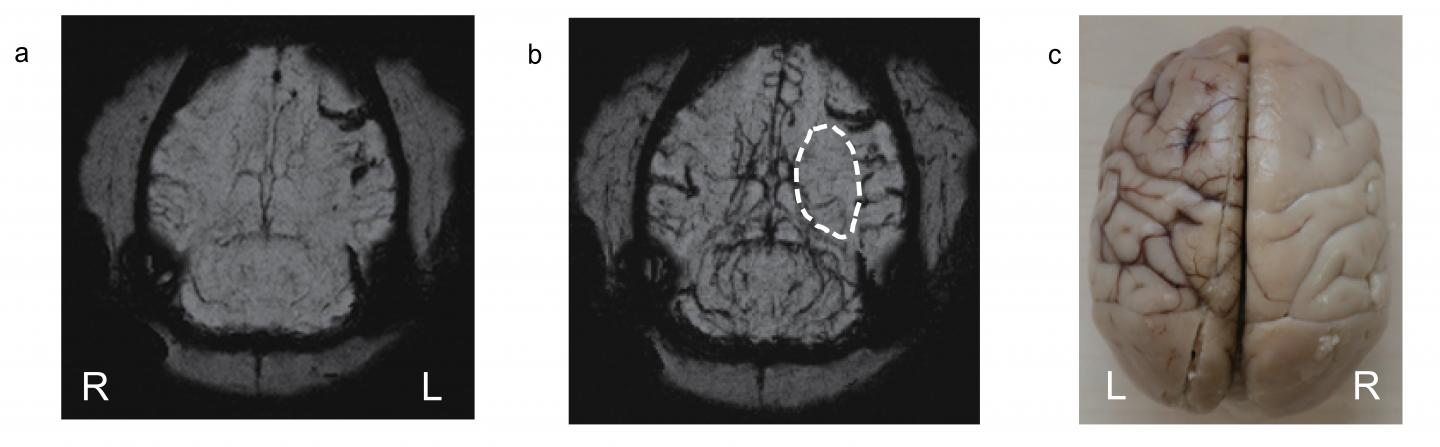

Whole Brain Imaging of a Monkey's Brain with Ischemia (IMAGE)

The PEG-IONCs contrast agent was used to dynamically follow an ischemia on the left side of a monkey's brain. After injecting PEG-IONCs (b) the details become clearer.